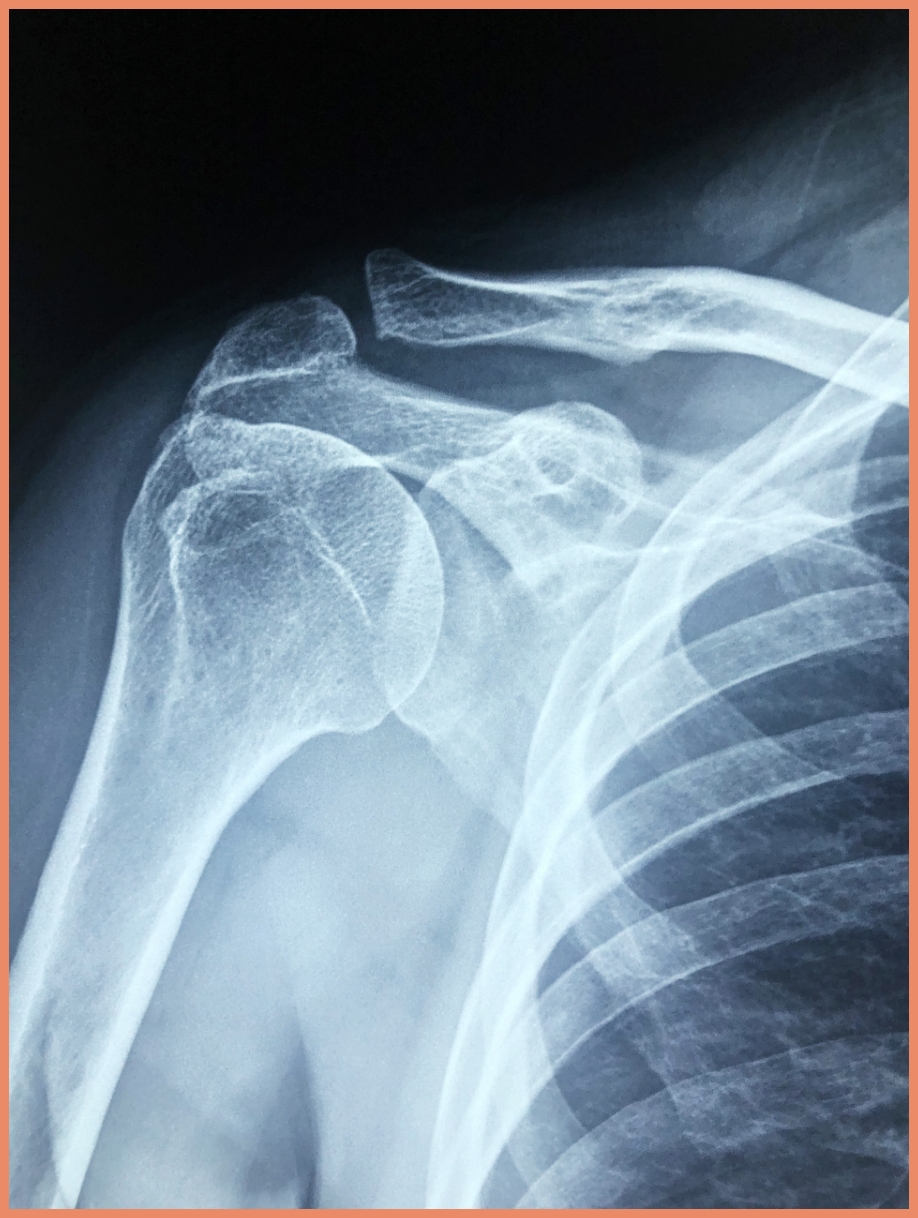

어깨 관절은 인체에서 가장 복잡한 관절 중 하나입니다. 상완골, 견갑골, 쇄골로 구성되어 있으며, 이들을 둘러싸고 있는 회전근개라는 네 개의 근육(극상근, 극하근, 견갑하근, 소원근)이 있습니다. 어깨충돌증후군은 이 회전근개가 견봉돌기라는 뼈와 부딪히면서 발생하는 질환입니다.

2. 영상학적 검사

- X-ray: 뼈의 구조적 이상 확인

- MRI: 연부조직 손상 정도 확인

- 초음파: 실시간 동적 검사 가능